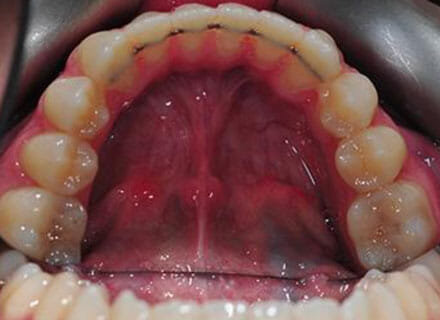

This patient came to us because she hated her smile: it was too narrow, the upper front teeth were all crowded into each other and twisted. She couldn’t eat a sandwich properly with the front teeth because of the gap – the open bite. We were able to expand both jaws to make space to align all the teeth without having to extract – in about 18 months using clear brackets.